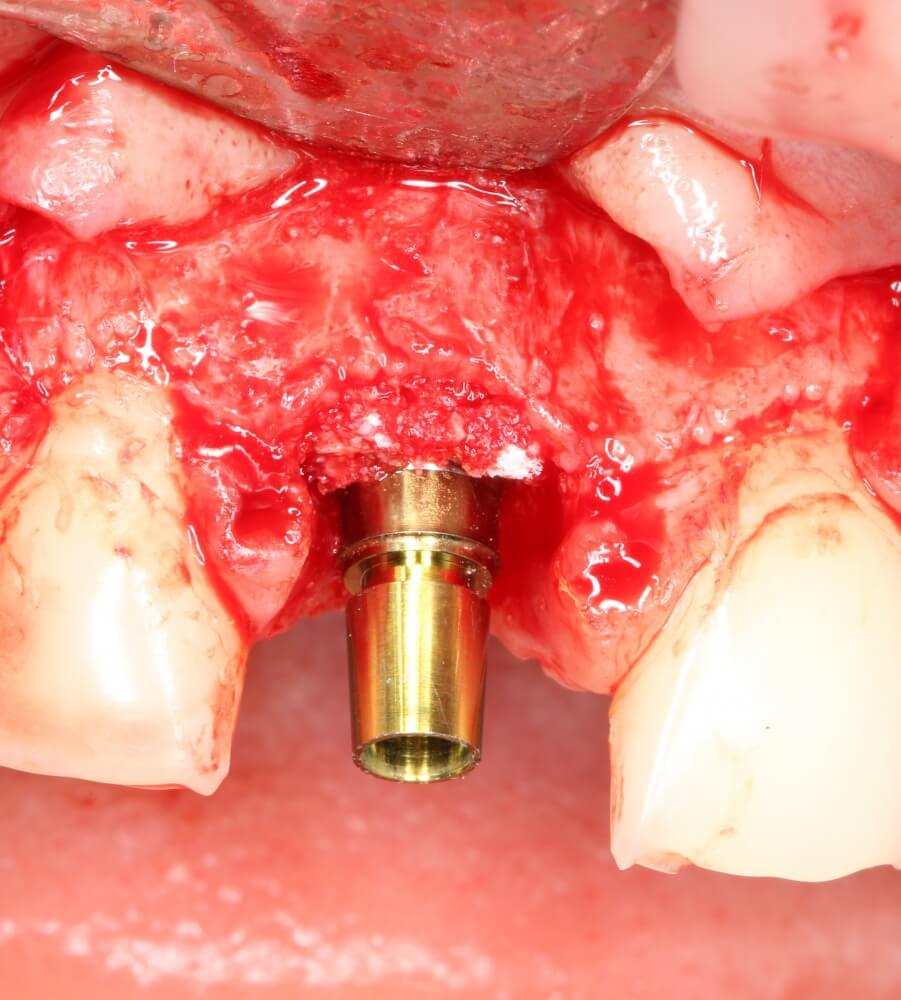

Рекомендации по установке имплантов. Для всех. Часть V.